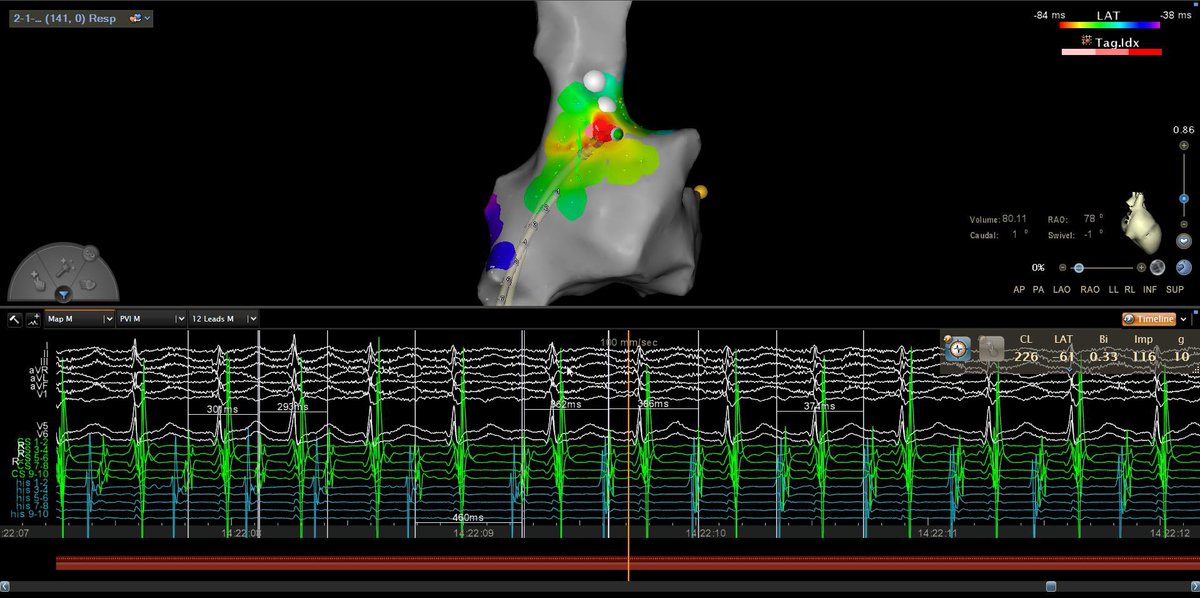

Impact of Left Atrial Posterior Wall Isolation using Pulsed-field Ablation in Patients Undergoing Repeat Catheter Ablation for Atrial Fibrillation #OpenAccess heartrhythmjournal.com/article/S1547-…